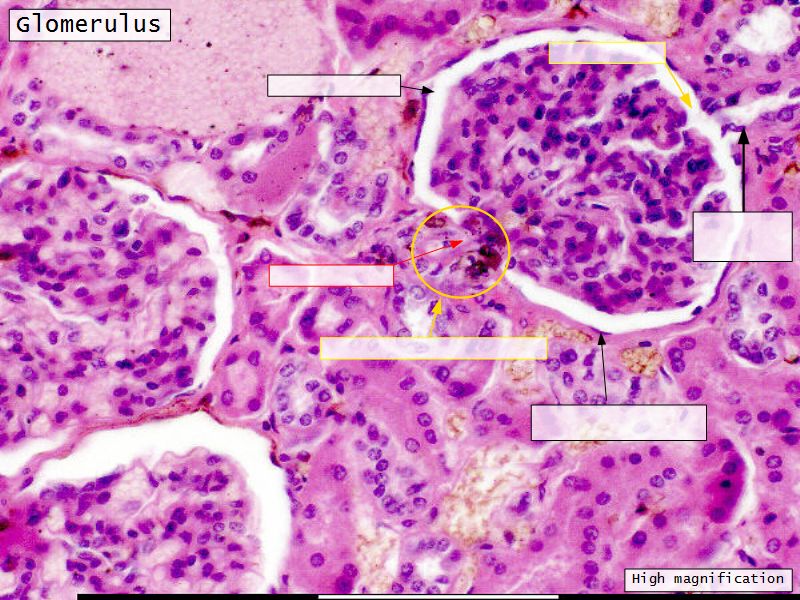

Renal corpuscle

- Two sides

- Vascular pole

- Tubular pole

Epithelium layers

- Capillary endothelium

- Visceral layer of epithelium

- Podocytes

- Resting on glomerular basement membrane

- Capsular space

- Parietal layer of epithelium

- Simple squamous epithelium

Juxtaglomerular complex

Area where distal convoluted tubule return to glomerulus and pass through the notch between the afferent and efferent arterioles. Modification of the wall of the tubule and afferent arteriole and presence of specialised cells in the connective tissue.Modifications

- Distal convoluted tubule

- Macula densa

- Narrow epithelial cells

- Nuclei densely packed

- CT cells

- Laci cells

- Similar to mesangial cells

- Afferent arteriole

- Modified smooth muscle cells

- Juxtaglomerular cells

- Secretory function

Capillaries

- Supported by

- Mesangial cells

- Mesangial matrix

- Phagocytic

- Maintain basement membrane

- Remove macromolecular deposits